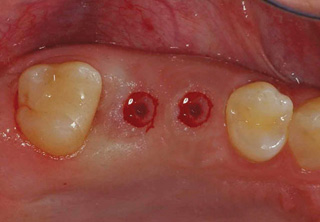

청담네오플란트 원데이 임플란트

하루만에 발치와 임플란트 식립을 동시에!

일반적으로 살릴 수 없는 치아를 발치하면, 2~3개월의 잇몸뼈 회복기를 거친 후 임플란트를 식립하게 됩니다. 하지만 잇몸뼈의 소실이

심하지 않은 경우 임플란트의 전체 치료기간 단축과 환자분의 불편감을 최소화하기 위해 내원 당일 발치 및 임플란트 식립을 진행할 수 있습니다.

필요에 따라 치조골 이식이 필요할 수 있으며, 가능한 경우 당일 임시 보철물 장착까지 해드려 심미적 기능을 회복할 수 있습니다.